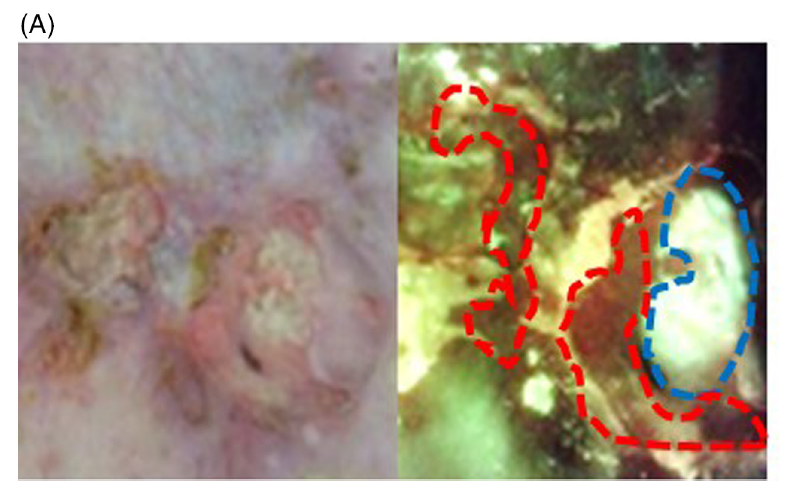

Skin Pigmentation Impacts the Clinical Diagnosis of Wound Infection: Imaging of Bacterial Burden to Overcome Diagnostic Limitations

Johnson J. et al. JREHD 2023

Bacterial Fluorescence Imaging to Address Racial Inequities in Wound Infection Assessment

Andersen, CA et al. Adv Skin & Wound Care 2024